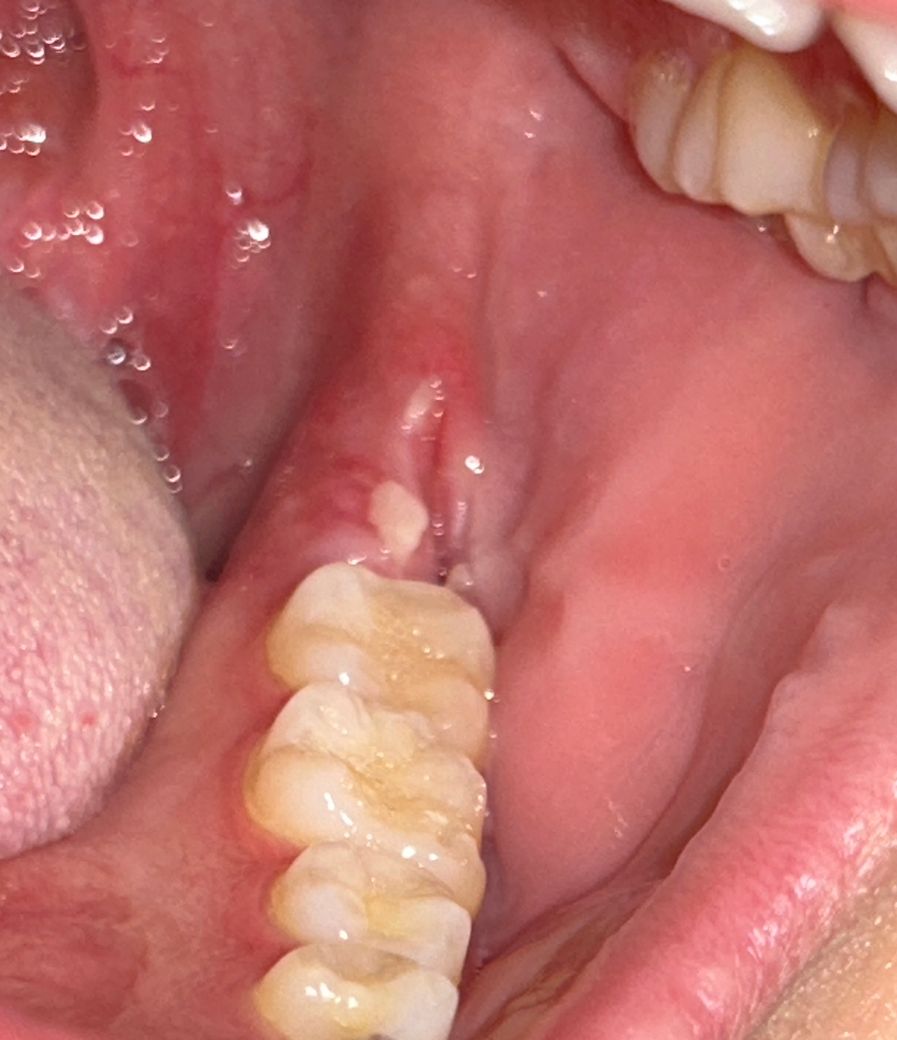

사랑니 실밥 제거 후 잇몸 벌어졌는데 괜찮은건가요?

화요일에 사랑니 뽑고 진통제를 먹어도 통증이 너무 심해서 목요일에 병원에 가서 실밥을 풀었더니 통증이 사라졌습니다. 결국 일주일이 지나지 않았을 때 빠르게 실밥 제거를 했는데 잇몸이 벌어졌습니다. 이거 괜찮은거 맞나요…? 다시 붙지는 않는건가요?

• 1번 째 사진

사랑니 실밥 제거 후에는 잇몸이 약간 벌어져있는 것이 보통이며 사진상 문제는 없어보입니다.